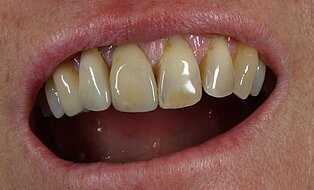

Vom Langzeitprovisorium zur TEK 1 Arbeit